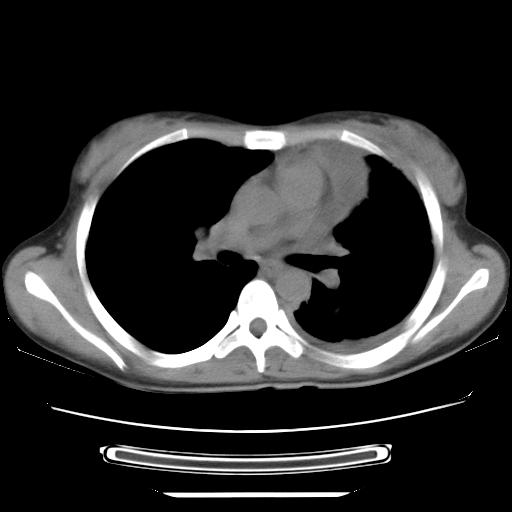

标题: CT21561:外院胸片提示胸腔积液,行CT检查。 [打印本页]

女,29岁,胸部不适,在外院胸片提示胸腔积液,到我院ct检查。

纵膈窗